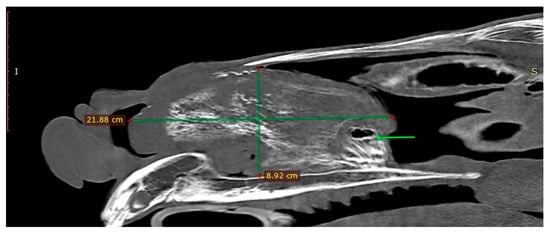

The endoscopic examination of the right nostril revealed the rightward bending of the nasal septum; an examination of the left side was unavailable due to the presence of the mass. Computed tomography of the head was performed under general anesthesia in dorsal recumbency. The patient was sedated with detomidine (0.02 mg/kg) prior to anesthetic induction with diazepam (0.1 mg/kg) and ketamine (2.2 mg/kg). Anesthesia was maintained using isoflurane (induction 5%, maintenance 2–3%). CT images were acquired with a Revolution 750 CT scanner, GE Healthcare Corporation, Chicago, IL, USA (120 kV, 280 mA, at 1.3 mm slice thickness). Two-dimensional tomographic sections were viewed using the RadiAnt DICOM 2020.2.3 software. Multiplanar image reconstructions allowed for the identification of the exact location of the mass, which extended from the level of Triadan 208 to the rostral part of the nasal cavity. The space-occupying lesion was well defined, heterogeneous, and measured approximately 22 × 9 × 5 cm (length × height × width) with internal zones of calcification (Figure 3). The mass caused the deformation and compression of the left dorsal and ventral nasal conchae, the deviation of the nasal septum, and the thickening of the right dorsal and ventral nasal conchae (Figure 4a). The tooth was displaced palatally to the nasal cavity, and the morphology was abnormal due to hypoplastic reserve, clinical crown and roots, enlarged infundibula, and variable radiodensity. The apex of 208 was deformed and had a direct connection to the mass (Figure 4b). The sinuses appeared normal.

Figure 3.

Sagittal CT image obtained left to sagittal line (bone algorithm, WW1500, WL 300). The mass length × height are indicated with green lines. Connection between the mass and the Triadan 208 is present (green arrow).